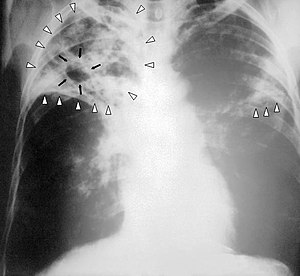

TBC merupakan singkatan dari Tuberkulosis, seringkali disingkat TB. TBC pun seringkali identik dengan penyakit paru, sehingga dikenal istilah medis TB Paru. Meskipun begitu, sebenarnya kuman TBC bisa menyebabkan infeksi di luar jaringan paru, seperti otak, kelenjar getah bening, ginjal. tulang dan persendian.

Infeksi TB bisa berupa stadium infeksi primer yang sering kali tanpa gejala, kemudian menjadi infeksi laten atau menjadi infeksi aktif. Diperkirakan 95% kasus infeksi TBC primer tidak menunjukkan gejala. Infeksi TBC tidak menular pada stadium primer dan laten, namun menular pada stadium aktif.